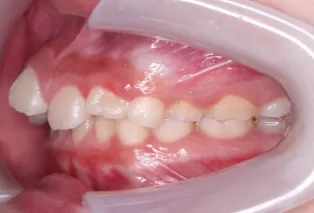

Intraoral photos